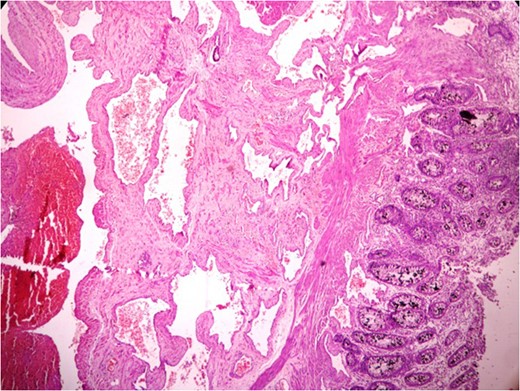

Markedly edematous and thickened mucosa due to vascular malformation.

Thickened wall with tiny cystic spaces in mucosa, muscularis propria and serosa of the wall (inset: histopathological picture of the same area).